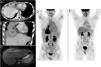

Varón de 14 años sin antecedentes de interés que consulta por síndrome febril de 6 meses de evolución. Analíticamente destacaban leucocitosis y elevación de la PCR y de los niveles séricos de IgG, específicamente de la IgG4. La tomografía computarizada, la resonancia magnética y la PET/TC mostraron una masa mediastínica anterior paradiafragmática derecha de aspecto infiltrante con realce heterogéneo intenso (figs. 1A-C) y marcado hipermetabolismo (fig. 1D). El estudio anatomopatológico tras biopsia percutánea reveló una lesión inflamatoria secundaria a enfermedad relacionada con IgG4. Tras 4 meses de tratamiento con glucocorticoides se produjo la total resolución del cuadro (fig. 1E).

Tomografía computarizada torácica y abdominopélvica con contraste intravenoso en planos axial (A) y coronal (B), donde se observa la masa mediastínica anterior con realce heterogéneo, de aspecto infiltrante (flechas rojas). Imagen de la RM potenciada en T2 con supresión grasa (C) en la que se identifica la masa mediastínica anterior hiperintensa (flecha roja). La lesión era marcadamente hipermetabólica en las imágenes de PET/TC iniciales (SUVmáx=11,9) (D) y desapareció en la PET/TC transcurridos 4 meses tras comenzar el tratamiento (E).